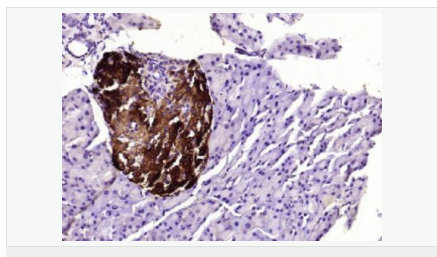

| 產品應用 | WB=1:500-2000 ELISA=1:5000-10000 IHC-P=1:100-500 IHC-F=1:100-500 ICC=1:100-500 IF=1:100-500 (石蠟切片需做抗原修復) not yet tested in other applications. optimal dilutions/concentrations should be determined by the end user. |

| 產品介紹 | This gene encodes an aldo-keto reductase that catalyzes the NADPH-dependent reduction of pteridine derivatives and is important in the biosynthesis of tetrahydrobiopterin (BH4). Mutations in this gene result in DOPA-responsive dystonia due to sepiaterin reductase deficiency. A pseudogene has been identified on chromosome 1. [provided by RefSeq, Jul 2008] Function: Catalyzes the final one or two reductions in tetra-hydrobiopterin biosynthesis to form 5,6,7,8-tetrahydrobiopterin. Subunit: Homodimer. Subcellular Location: Cytoplasm. Post-translational modifications: In vitro phosphorylation of Ser-213 by CaMK2 does not change kinetic parameters. DISEASE: Defects in SPR are the cause of dystonia DOPA-responsive due to sepiapterin reductase deficiency (DRDSPRD) [MIM:612716]. In the majority of cases, patients manifest progressive psychomotor retardation, dystonia and spasticity. Cognitive anomalies are also often present. The disease is due to severe dopamine and serotonin deficiencies in the central nervous system caused by a defect in BH4 synthesis. Dystonia is defined by the presence of sustained involuntary muscle contractions, often leading to abnormal postures. Similarity: Belongs to the sepiapterin reductase family. SWISS: P35270 Gene ID: 6697 Database links: Entrez Gene: 6697 Human Omim: 182125 Human SwissProt: P35270 Human Unigene: 301540 Human Important Note: This product as supplied is intended for research use only, not for use in human, therapeutic or diagnostic applications. |